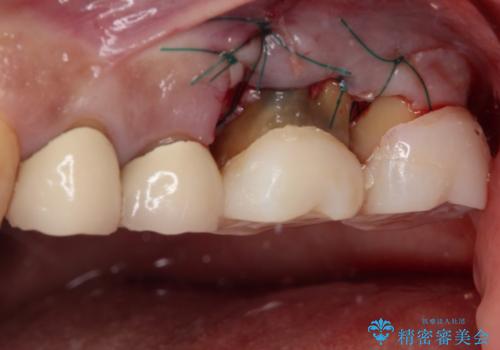

インプラントや歯周外科処置を用いた奥歯の補綴治療

左側は骨欠損が著しいことが予想されるため、骨造成術並びに歯肉移植術を併用することとしました。

歯肉縁下にまで虫歯が及んでいたため、歯冠長延長術を行い、清掃性の改善を試みます。

仮歯がない状態を極力避けたいとのことで、外科処置を少しずつ進めていくことになり、治療期間は2年間を要しました。